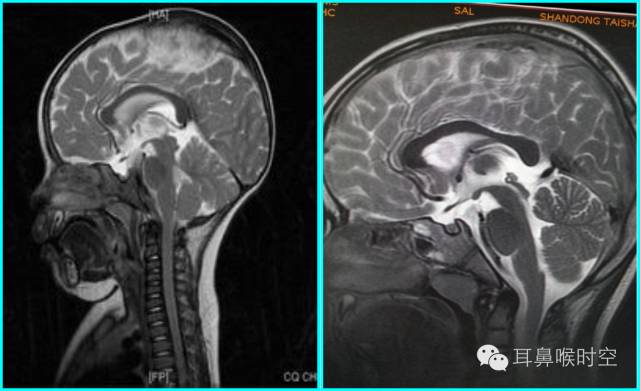

MRI

根据经典Fujioka 等 X 线平片测量法原理:

A/ N 比:测量腺样体最大厚度与自硬腭上缘到颅底蝶枕骨的软骨结合部的距离之比

PAS:后气道间隙(pharyngealairway space , PAS)的宽度(软腭表面与腺样体表面之间有效气道宽度)。

采用SE 序列矢状面T1WI

选择正中矢状面,分别测量两条径线(图1、2)

N 线:即从蝶骨体2枕骨斜坡的软骨结合部后缘(O点)至硬腭与软腭上缘交界处的连线N

A 线:过O点沿枕骨斜坡下缘作延长线L,取腺样体下缘最凸点作L线的垂直线。

A/N比:分别测A、N值,计算A/N 比

正常组镰刀形(图4)、刀鞘形(图5)为主

镰刀形、刀鞘形,腺样体厚度较薄,下缘凹陷或平直,但均不下凸

肥大组子弹形(图6)、山丘形(图7)为主

肥大组:子弹形、山丘形,腺样体饱滿、下凸,象山丘样突出。在冠状面上腺样体表现为“马鞍形”和“倒置梯形”。

解剖结构:在MRSET1WI 鼻咽部正中矢状面图像上,由于采取薄层断面成像

可以直观显示腺样体本身

清晰显示蝶骨体与枕骨斜坡之间的软骨接合部、鼻后孔间隙、鼻甲、硬腭与软腭上缘的交界面、软腭、会厌软骨等结构

易于测量:非常容易画出A 线及N 线,及测量PAS,了解鼻后孔间隙、鼻甲大小、软腭厚度及后突程度

动态观察:利用MR电影可动态观察鼻咽部随呼吸运动的情况,大大丰富了诊断信息。

任意平面:MR扫描不受体位影响,可行任角度断面扫描与图像重建,从而保证其正中矢状面图像的质量

可重复性:MR是一种无创性检查,无X线辐射危害,不影响儿童生长发育和健康。

MRI表现:

多方位检查

有利于显示肥大的腺样体

呈等T1、长T2信号

增强时可强化